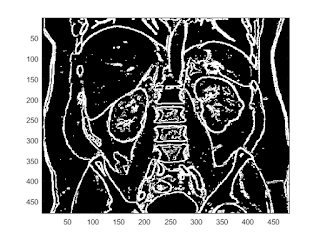

sobel edge filter

b = fspecial('sobel'); I2 = conv2(I,b,'same'); imagesc(I2); colorbar

imagesc(abs(I2)>200)